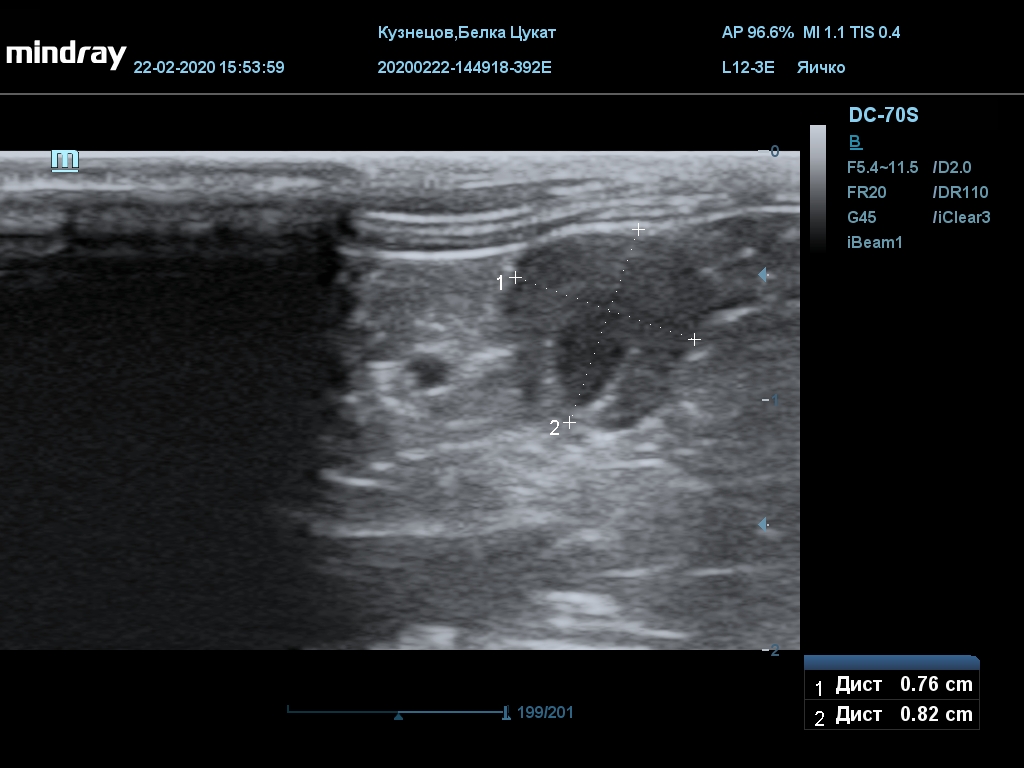

УЗИ

(почки, мочевой пузырь и, предположительно, простата)

Обращаю внимание, что делала УЗИ и писала заключение узист, которая специализируется на кошках и собаках, поэтому она сделала узи и описала, как смогла, но тонкостей грызунячьей анатомии она не знает.

Приложил только фото, есть ещё пара видео, но не знаю, как тут выложить, и надо ли.

Мочевой пузырь объём 12,1 х 7,6 х 11 мм. Стенка не утолщена, 0,5 мм, содержимое не однородное, до половины объёма гипоэхогенная мелкодисперсная взвесь. Макс. размер включений 0,8 мм. Теней нет.

Каудальнее мочевого пузыря визуализируется округлая структура размером 11,1 х 8,3 мм с ровными контурами гипоэхогенная однородная, с признаками васкуляризации.

Почка левая ровная, размер 12 х 7,6 х 8,2 мм. Контур ровный чёткий. КМД отсутствует, лоханка расширена незначительно, объёмных включений не выявлено.

Почка правая ровная, контур чёткий, размер 13,5 х 8,7 х 9,3 мм. Капсула визуализируется. КМД отсутствует, лоханка не расширена. Объёмные образования не выявлены.

Заключение: УЗпризнаки уролитиаза, объёмная структура каудальнее мочевого пузыря. Признаки расширения левой лоханки.

УЗИ

(почки, мочевой пузырь и, предположительно, простата)

Обращаю внимание, что делала УЗИ и писала заключение узист, которая специализируется на кошках и собаках, поэтому она сделала узи и описала, как смогла, но тонкостей грызунячьей анатомии она не знает.

Приложил только фото, есть ещё пара видео, но не знаю, как тут выложить, и надо ли.

Мочевой пузырь объём 12,1 х 7,6 х 11 мм. Стенка не утолщена, 0,5 мм, содержимое не однородное, до половины объёма гипоэхогенная мелкодисперсная взвесь. Макс. размер включений 0,8 мм. Теней нет.

Каудальнее мочевого пузыря визуализируется округлая структура размером 11,1 х 8,3 мм с ровными контурами гипоэхогенная однородная, с признаками васкуляризации.

Почка левая ровная, размер 12 х 7,6 х 8,2 мм. Контур ровный чёткий. КМД отсутствует, лоханка расширена незначительно, объёмных включений не выявлено.

Почка правая ровная, контур чёткий, размер 13,5 х 8,7 х 9,3 мм. Капсула визуализируется. КМД отсутствует, лоханка не расширена. Объёмные образования не выявлены.

Заключение: УЗпризнаки уролитиаза, объёмная структура каудальнее мочевого пузыря. Признаки расширения левой лоханки.